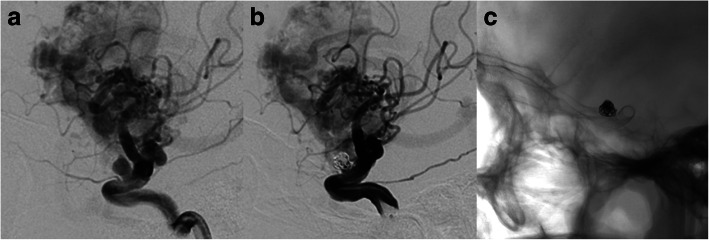

Fig. 4.

Case No. 4 has a V-B junction aneurysm with coexisting AVM supplied by both anterior (a) and posterior circulation (b). We deployed the PED from the lower 1/3 of basilar artery to the left VA and further coiled the aneurysm loosely (c). 3 months follow up indicated incomplete occlusion of the aneurysm (d)

Fig. 5.

Case No. 5 was an 8-year-old girl with a large V-B junction dissecting aneurysm (a), we overlapped two PEDs, coiled the aneurysm and sacrificed the left VA with a detachable balloon (b). At 3-month follow-up, the aneurysm was still patent but decreased in size (c)

Case No. 4 was 34-year old female complained a gradually aggravated headache for 3 months. DSA showed a V-B junction aneurysm. Besides the aneurysm, the patient suffered from an AVM (Spetzler-Martin 3) that received feeding arteries both from the anterior posterior circulation (Fig. 4a, b). We deployed the PED (4.25 mm*25 mm) from the lower 1/3 of basilar artery to the left VA and further coiled the aneurysm loosely to achieve favorable stasis of flow (Fig. 4c). 3 months follow up indicated incomplete occlusion of the aneurysm (Fig. 4d). Case No. 5 was an 8-year-old girl presented with ataxia, vomiting and nausea. DSA indicated a large V-B junction dissecting aneurysm (Fig. 5a). Learned from the experience of case 4, we decided to telescoping two PEDs (4.25 mm*35 mm) to achieve a better flow diversion effect. Control angiography suggested that there was no apparent stasis of angiographic agent due to the persistent blood flow from the contralateral VA. So we decided to coil the aneurysm and concomitantly to occlude the aneurysm with a detachable balloon (Balt, France) (Fig. 5b). The patient recovered from general anesthesia smoothly and discharged without any neurological deficit. 3 months follow up angiography indicated a certain degree of decrease in size and the patient was free from any symptom, yet the aneurysm was still partially embolised (Fig. 5c). So, knowing that the V-B junction aneurysm is quite refractory in nature, we treated case No. 6 (Fig. 6a) By overlapping 2 longest PEDs (4.25 mm*35 mm) to enhance the flow diversion effect and further occluded the contralateral VA with coils (Fig. 6b, c). It is inevitable to cover the perforating branches of basilar artery if you chose a 35 mm long PED. The patient experienced transient visual loss of both eyes, however, the patient completely recovered from these symptoms one day after operation. This patient is still on follow-up.